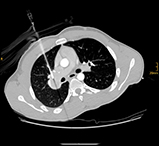

R20-Export_1_vs2 R20-Export_3_vs R20-Export_5_vs_2 R20-Export_7_vs

„Interventionelle Radiologie auf höchstem Niveau“: v.l.n.r: Biopsie einer Metastase eines Tumors der Speiseröhre durch die Wirbelsäule; Implantation einer vierfach verzweigten  Gefäßprothese in der Hauptschlagader zur Ausschaltung eines Aneurysmas; Biopsie eines Tumors in der Verzweigung des Hauptgallenganges mit zwei Biopsienadeln und die Biopsie eines Tumors in der rechten Lunge. (Bilder können durch anklicken vergrößert werden.)